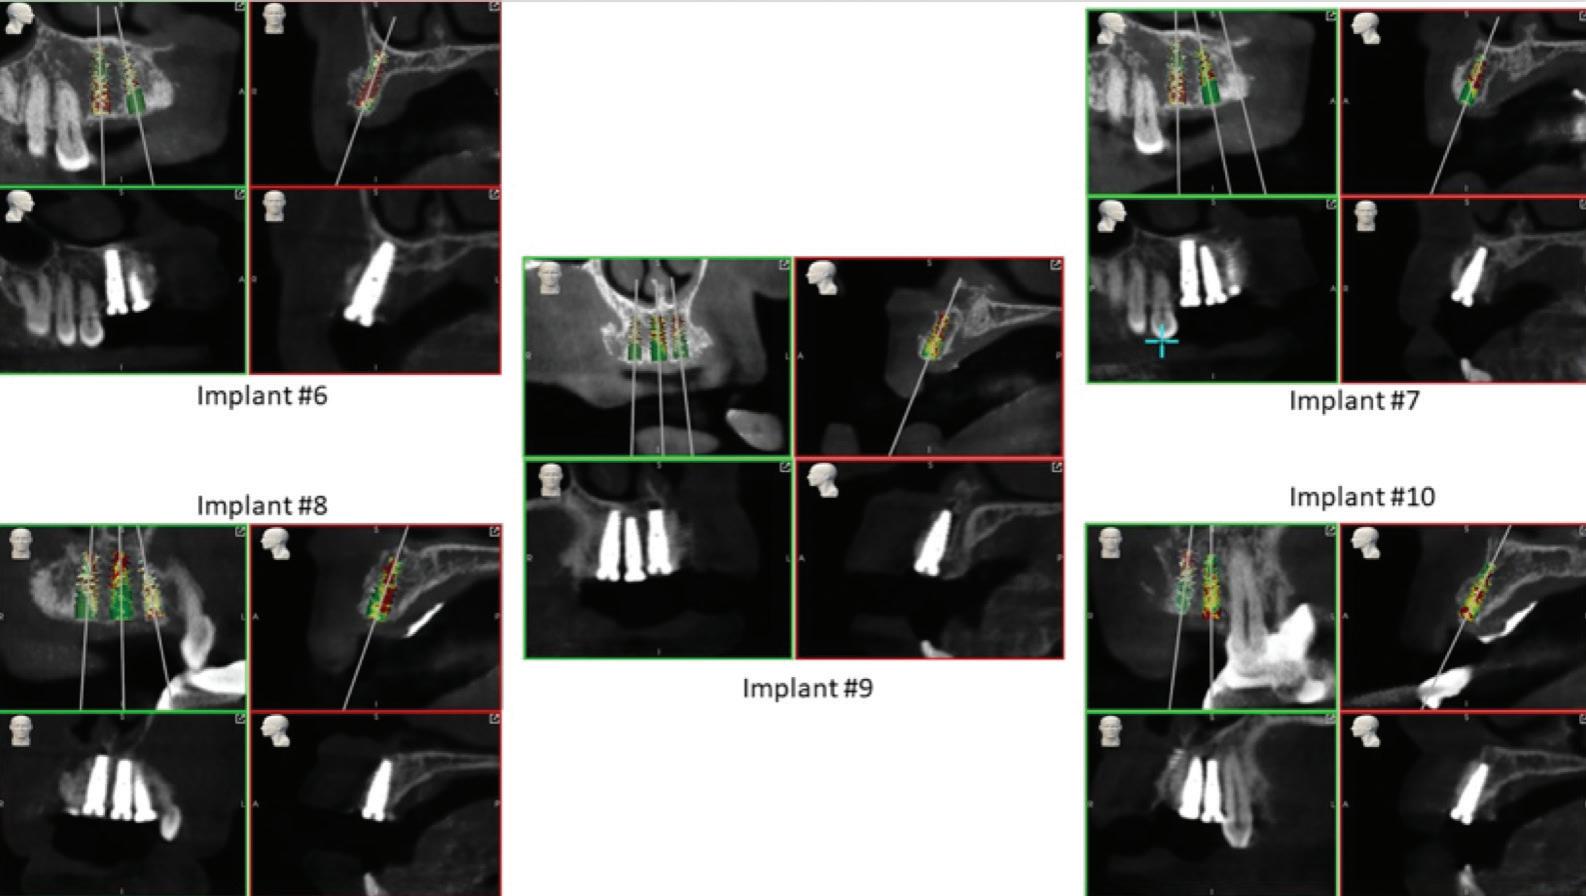

Tehnologia digitală redefinește terapiile implantare

• Chirurgia implantară cu cea mai inteligentă planificare și mai precisă execuție va necesita în continuare un finisaj protetic care funcționează biomecanic și realizează o estetică naturală ideală individuală. Dacă există un aspect al tratamentului protetic cu provocări în era digitală, acesta ar consta în munca artistică minuțioasă a ceramistului, cu modelarea și pictarea dinților pentru a imita natura.

Colaborarea profesională și planificarea ghidată protetic sunt esențiale pentru rezultate predictibile de succes.